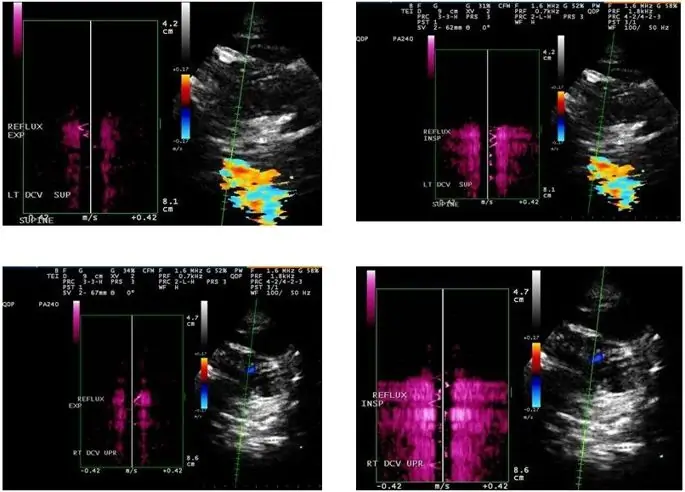

Из-за преимуществ DS в обнаружении внутрипросветной венозной патологии, он был первоначально продвинут в качестве метода выбора для скрининга экстракраниальных венозных аномалий и вариантов развития, показательных для CCSVI (18, 27). Диагноз CCSVI основан на результатах гемодинамики и визуализации, которые используют DS для изучения глубоких мозговых вен, IJV и позвоночных вен (VV) как в прямом, так и в положении лежа на спине. DS также может оценивать гемодинамические последствия нарушения оттока, в то время как ультразвук в B-режиме обнаруживает структурные венозные внутрипросветные аномалии (Figure 1E, F) (18, 27, 31, 33, 109, 112). Zamboni et al. создали набор из пяти критериев DS VH, по которым пациенты с MS отличались от здоровых контролей со 100% специфичностью и чувствительностью (18, 27) (рис. 1). Однако в своей первоначальной публикации (18) они не рекомендовали точные технические процедуры для применения протокола ни в исследовательских, ни в обычных клинических условиях. Первая попытка определить стандартизированный протокол сканирования CCSVI была недавно представлена (98). Совсем недавно Международное общество нейроваскулярных заболеваний (ISNVD) разработало более всеобъемлющий согласованный документ, в котором приняли участие более 40 международных экспертов в области визуализации DS. DS был предложен как стандартизированный инструмент скрининга для определения статуса CCSVI (33). Протокол предлагает использовать количественные измерения для определения функциональных аномалий, таких как скорость и объем кровотока (рис. 2), которые могут быть потенциально более надежными при оценке степени обструкции венозного оттока в IJVs. Он также уточняет первоначально предложенные критерии VH. Еще недавно Европейское общество нейросонологии и церебральной гемодинамики (ESNCH) выразило серьезные опасения относительно точности предложенных критериев для CCSVI при MS (32), и предложило центральное слепое чтение DS как часть недавнего многоцентрового итальянского CoSMo исследование, изучающее распространенность CCSVI у пациентов с РС, контрольной группы и пациентов с ОНД (113).

Пример измерения скорости (A) и объема (B) в течение четырехсекундной фазы во внутренней яремной вене (IJV)

Основная критика рекомендованного протокола DS заключается в том, что его воспроизводимость зависит от уровня подготовки и навыков оператора, и его нелегко ослепить и стандартизировать ни в исследовательской, ни в клинической практике (29-33, 87). Кроме того, значение критериев CCSVI VH является спорным, поскольку они объединяют функциональные и структурные внутри- и экстракраниальные венозные аномалии / варианты развития в одном бинарном композите. Zamboni et al. использовал ≥2 ненормальных критериев DS VH в качестве порога для классификации диагнозов CCSVI (18, 27). Дихотомическая переменная конструкция диагноза CCSVI, основанная на произвольном решении, смещенном в сторону характеристик первоначально изученной популяции и полученных результатов без дальнейшего тестирования и валидации наборов данных (18, 27), может способствовать объяснению основных несоответствий в распространенных результатах CCSVI между различными исследованиями колеблется от 0 до 100% (18, 27, 34, 78-98, 100, 101, 114). Оценка второго критерия CCSVI (рефлюкс в глубоких мозговых венах) (рис. 3) особенно противоречива, поскольку направление кровотока в венах, соединяющих кортикальные и глубокие вены, может значительно различаться вследствие физиологического межиндивидуального изменения венозная анатомия головного мозга (30, 32, 33, 87).

Пример рефлюкса в глубоких мозговых венах с использованием качественного допплеровского профиля (QDP). Допплеровский профиль на противоположных сторонах базовой линии.